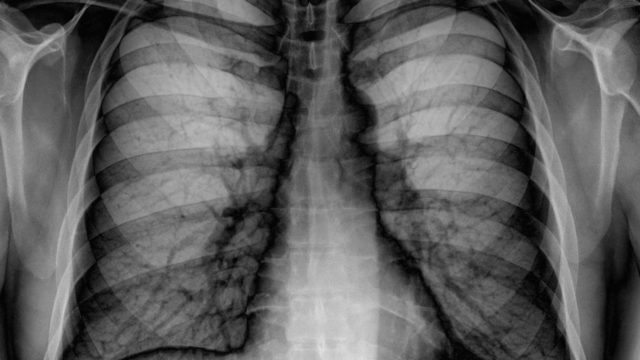

County: Blue Line Trolley Riders Possibly Exposed to Tuberculosis

The county’s Tuberculosis Program was working with the Metropolitan Transit System Tuesday to notify riders of the trolley’s Blue Line that they were potentially exposed to and are at risk for tuberculosis.

Chest x-ray Tuberculosis case